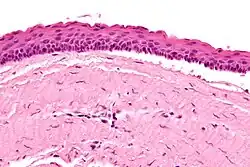

| Micrograph of an odontogenic keratocyst. H&E stain. | |

Odontogenic keratocysts have a diagnostic histological appearance. Under the microscope, OKCs vaguely resemble keratinized squamous epithelium;[15] however, they lack rete ridges and often have an artifactual separation from their basement membrane.[2]

The fibrous wall of the cyst is usually thin and uninflamed. The epithelial lining is thin with even thickness and parakeratinised with columnar cells in the basal layer which have focal reverse polarisation (nuclei are on the opposite pole of the cell).[13] The basal cells are an indication of the odontogenic origin as they resemble pre-ameloblasts. The epithelium can separate from the wall, resulting in islands of epithelium. These can go on to form 'satellite' or 'daughter' cysts, leading to an overall multilocular cyst.[10] Presence of daughter cysts is particularly seen in those with NBCCS.[13] Inflamed cysts show hyperplastic epithelium which is no longer characteristic of OKCs and can have resemblance to radicular cysts instead. Due to areas of focal inflammation, a larger biopsy is required for correct diagnosis of odontogenic keratocysts.[10]